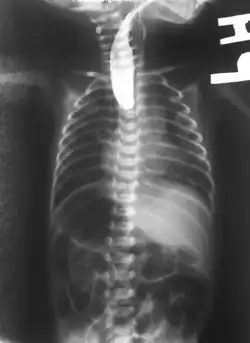

Plain x-ray with contrast in the upper esophagus above the atresia.

If any of the above signs/symptoms are noticed, a catheter is gently passed into the esophagus to check for resistance. If resistance is noted, other studies will be done to confirm the diagnosis. A catheter can be inserted and will show up as white on a regular x-ray film to demonstrate the blind pouch ending. Sometimes a small amount of barium (chalk-like liquid) is placed through the mouth to diagnose the problems. However, performing such an oral contrast study is not advised due to a risk of aspiration.[30]